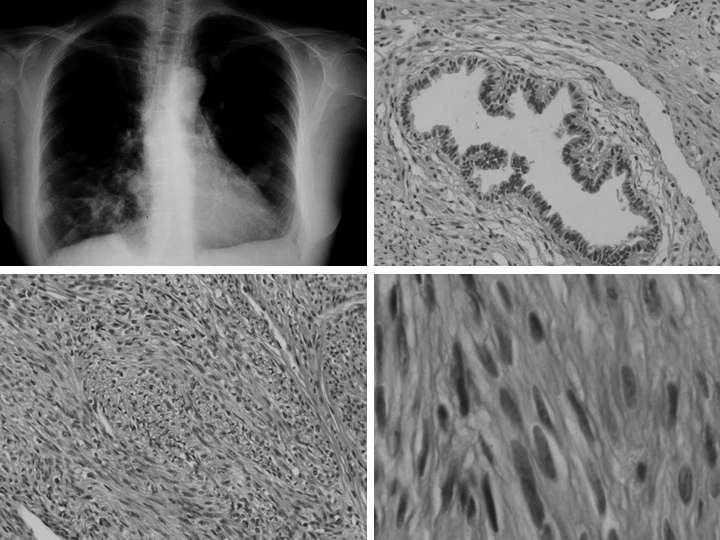

Presentamos el caso de una paciente de 54 años de edad, a quien se practicó una histerectomía (total con doble anexectomía) debido a múltiples miomas. En la pieza quirúrgica se observó la presencia de adenomiosis y de un pólipo endometrial. Ante la imagen en la radiografía anteroposterior de tórax en "suelta de globos" (fig. 1) descubierta en el estudio preoperatorio de la enfermedad uterina, se estudió a la paciente en el Servicio de Neumología, donde se solicitó una tomografía axial computarizada de tórax, en la que se observaron múltiples imágenes nodulares y sólidas, de tamaño diverso, que se distribuían en ambos campos pulmonares de manera difusa, con un patrón multinodular. Dichos hallazgos eran indicativos de enfermedad metastásica pulmonar de tumor primario desconocido. No se objetivaron adenomegalias mediastínicas ni retroperitoneales. Se aconsejó la realización de una colonoscopia, en la que no se observó enfermedad evidente. Lo mismo sucedió con los estudios citológicos del aparato respiratorio y con la fibrobroncoscopia (estas últimas pruebas realizadas tras la intervención quirúrgica ginecológica referida). Se remitió a la paciente al Servicio de Cirugía Torácica para la realización de biopsia mediante resección en cuña de 2 nódulos pulmonares bilaterales mediante videotoracoscopia. Las lesiones, de 2,5 y 2 cm de dimensiones máximas, mostraban una tonalidad blanquecina y un aspecto fasciculado, siendo la consistencia firme al corte. Su estudio histológico permitió observar una lesión fusocelular, donde las células presentaban citoplasmas ligeramente eosinófilos y núcleos fusiformes centrales con bordes romos "en cigarro puro" sin nucléolo, atipia ni mitosis evidentes. Asimismo, la seriación exhaustiva de la pieza quirúrgica no demostró focos de necrosis tumoral, áreas pleomórficas o mayor atipia celular. Con todos estos datos histológicos, y teniendo en cuenta los antecedentes y la situación clínica de la paciente, se estableció el diagnóstico de leiomioma benigno metastásico de localización pulmonar. Tras 2 años de seguimiento la paciente no ha presentado síntomas derivados de su enfermedad ni ha precisado tratamiento específico.

Fig. 1. Radiografía anteroposterior de tórax (imagen superior izquierda) y detalles microscópicos de la lesión (*20 y *40 aumentos).